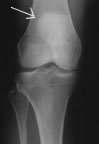

Take a look at this x-ray. The bones are pale, and the spaces are dark. If one bone overlies another you may see the outline of both, but they appear to be on the same plane (see arrow, showing the pale circle of the patella overlying the femur). With a single film one can thus see only the one dimension. This view is called an 'AP' view (antero-posterior).

In an AP view the patella shows as a vague circle over the femur bone. Little information can be gleaned other than its height and basic outline, and maybe fracture (break) lines (which appear dark).